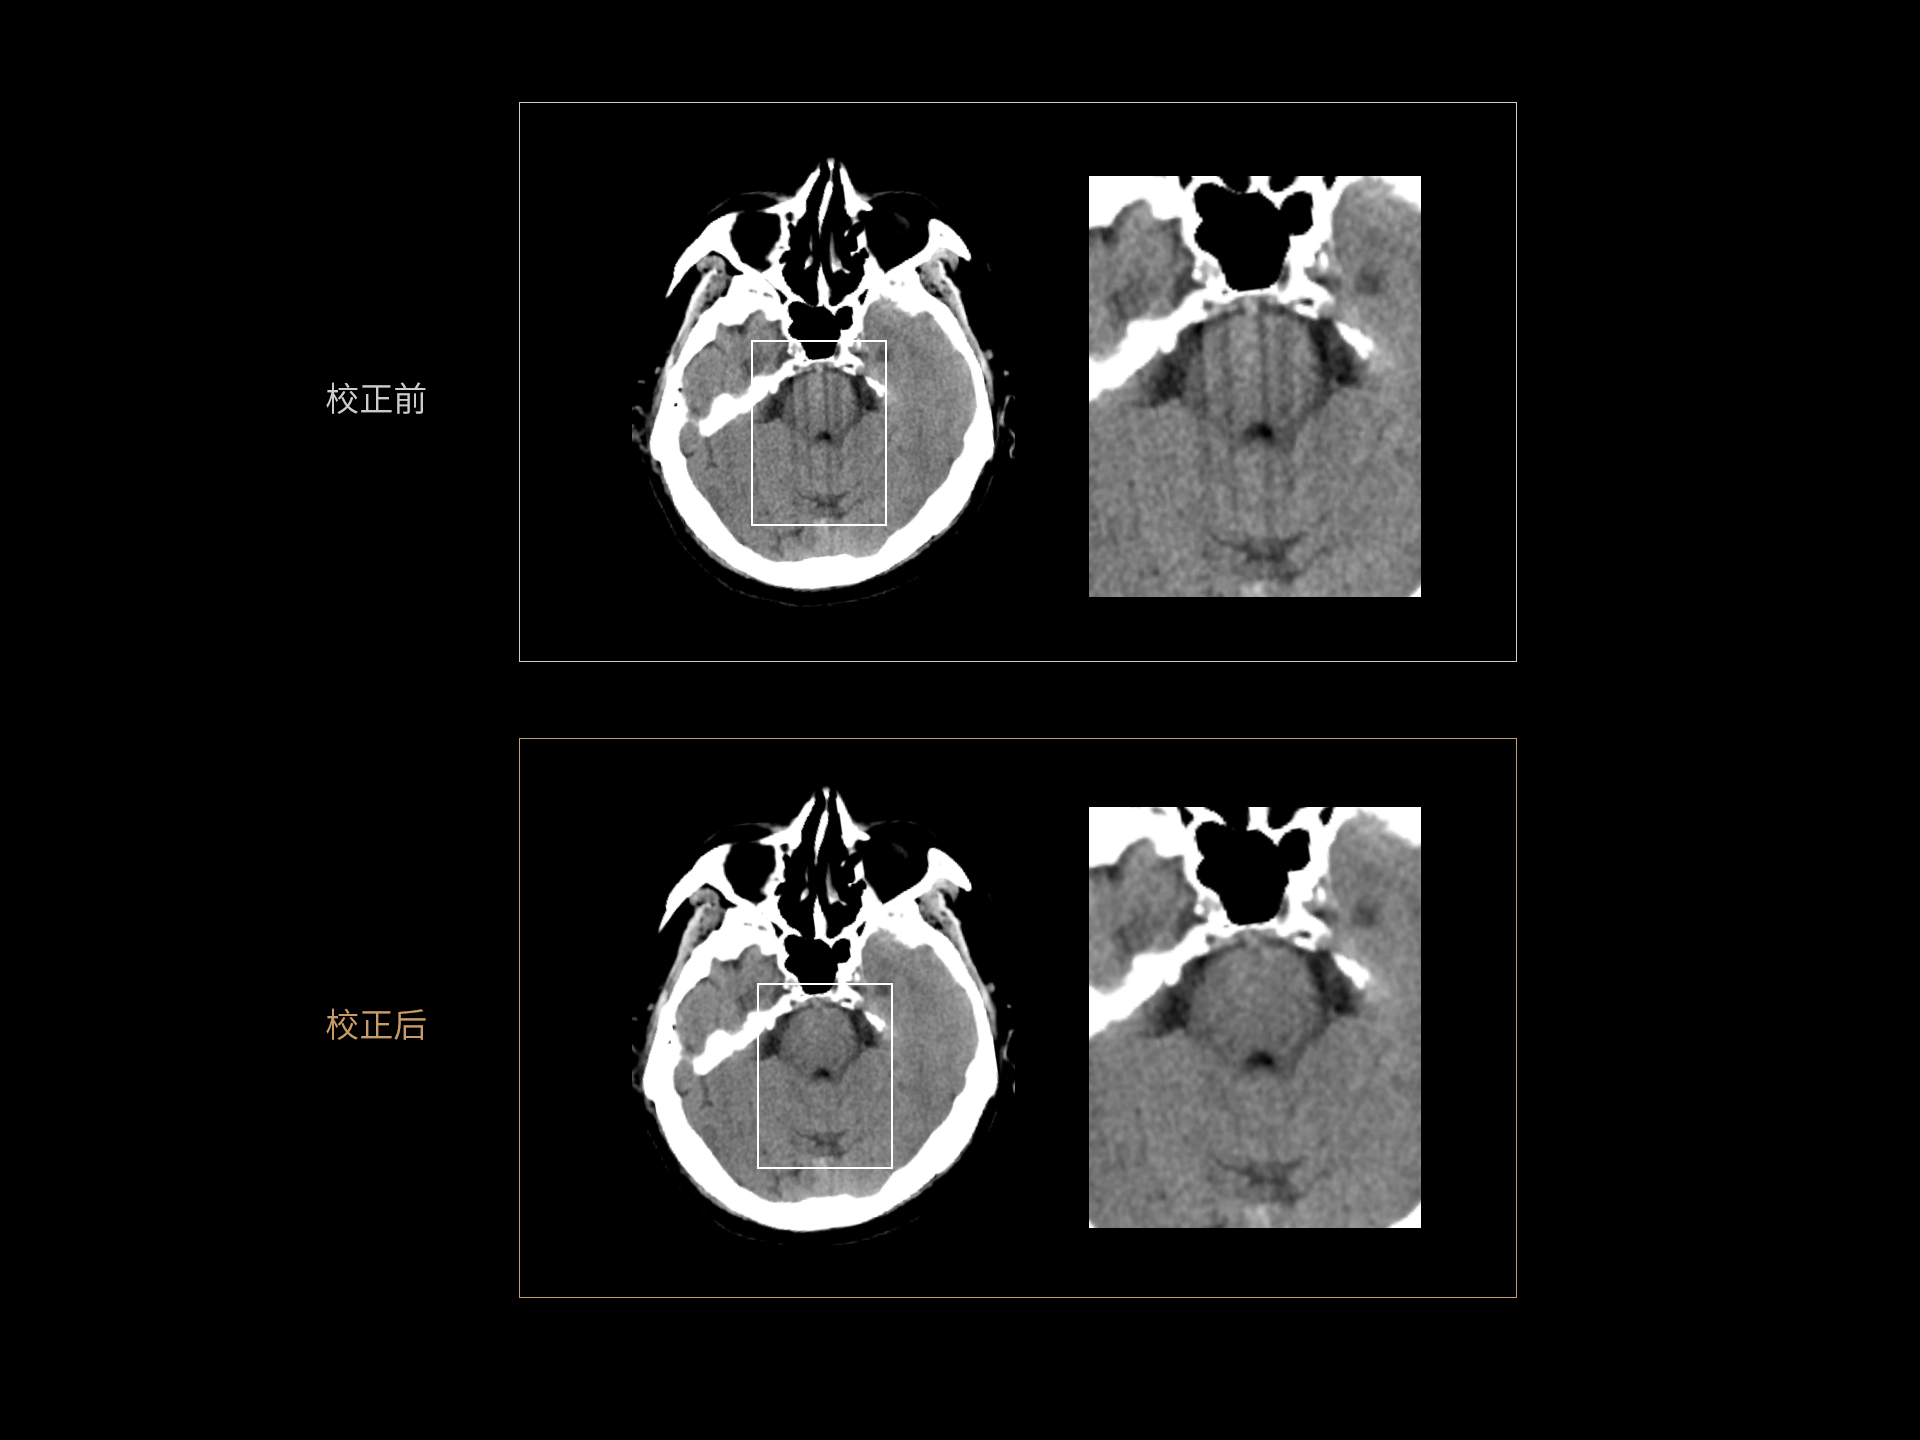

AI运动感知重建 消除头部运动伪影

Motion Freeze技术:基于深度学习技术校正头部运动伪影,保持头部结构清晰显示。

选用临床无运动伪影的图像作为金标准图像,模拟出不同场景下的运动形式,获得含有运动伪影的图像,从而解决了金标准数据与伪影数据的获取、匹配难题。Motion Freeze构建了独特的3D卷积神经网络,在去除运动伪影的同时,保障图像的空间与密度分辨率不受影响。

Motion Freeze临床应用范围广,可应用于头部平扫、增强、血管造影(CTA)和灌注(CTP)等临床场景;改善因疾病、紧张等因素导致的头部运动伪影,减少不必要的重复扫描、从而降低检查的辐射剂量。

AI 运动感知重建 Motion Freeze

头部运动深度学习重建:消除头部运动引起的条状伪影,还原脑部结构,利于准确诊断;去除运动伪影功能,可以减少重复扫描次数,提升工作效率。